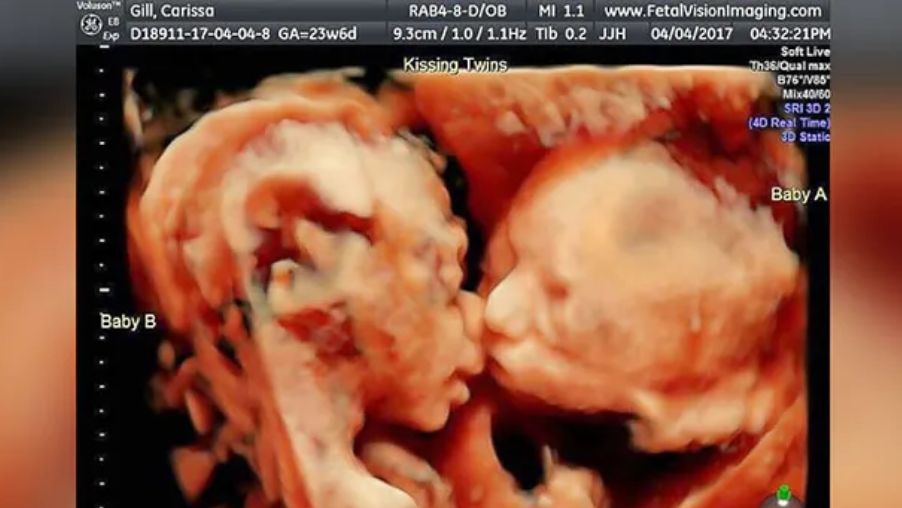

Carissa Gill i Randy Good są rodzicami dwóch ślicznych dziewczynek, bliźniaczek, których zdjęcie - jeszcze z czasów, kiedy były w brzuchu mamy - widziało pół świata. Czy dziewczynki naprawdę pocałowały się na oczach lekarza? Zdjęcie, które wykonano aparatem USG, jest niesamowite!

Carissa Gill była w 24. tygodniu ciąży. Pewnego dnia poszła do Fetal Vision Imaging w Pensylwanii na rutynowe badanie. Chciała dowiedzieć się, czy bliźniaczki, które są w jej brzuchu, rozwijają się w prawidłowy sposób.

Jak się okazało, bliźniaczki były zdrowe, jednak to, co zobaczył lekarz przy okazji, podczas wykonywania badania USG 4D, zupełnie go zszokowało. Nie tylko jego, bowiem niemniej zdziwiona była mama dziewczynek, a także tata dzieci - Randy Good, kiedy lekarz przesunął monitor w jego stronę.

Nietypowe ułożenie dwóch dziewczynek w brzuchu mamy wyglądało tak, jakby te się pocałowały. Też to widzicie?

Na tradycyjnym USG nigdy nie były tak blisko siebie, a tu leżały twarzą w twarz. (...) Mogłam obserwować, jak ruszają ustami, jak się kąpią nawzajem, ale to, co się stało na końcu, bardzo mnie wzruszyło. Bella nagle pocałowała Callie w policzek! - stwierdziła Carissa Gill, podaje Daily Mail.